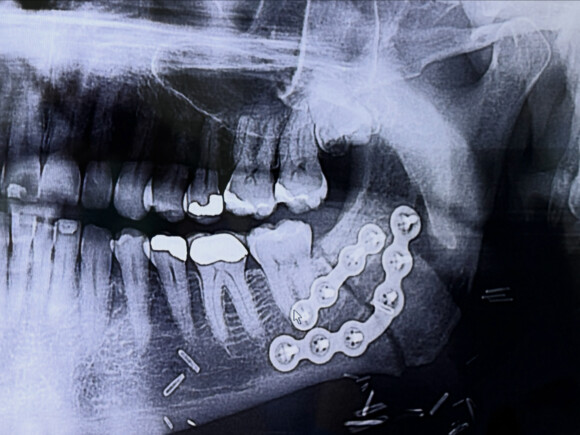

This Is Not Where I Thought They Split My Jaw

I saw my dentist today for the first time since last September’s surgery. This is not where I thought they split my jaw. All this time I was thinking it was front and center when it turns out it was behind my last molar. This also explains why they didn’t have to remove any teeth and why I have no feeling in my lower jaw; they had to cut the nerve!